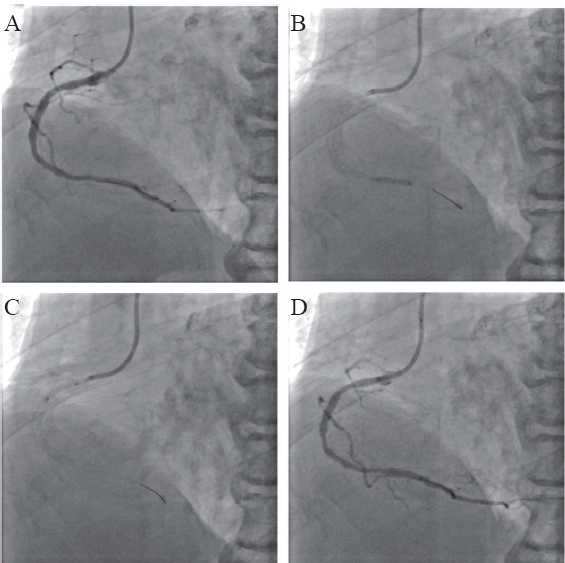

图3 一例NSTEMI患者行回旋支药物球囊扩张术CAG图

A:回旋支药物球囊扩张术前;B、C:药物球囊(2.75 mm×26.00 mm、3.0 mm×17.0 mm)治疗过程;D:药物球囊治疗术后